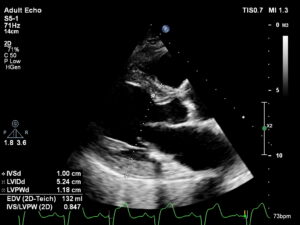

Ecocardiograma

Ecocardiograma: O exame que revela a saúde do seu coração

A importância do Ecocardiograma